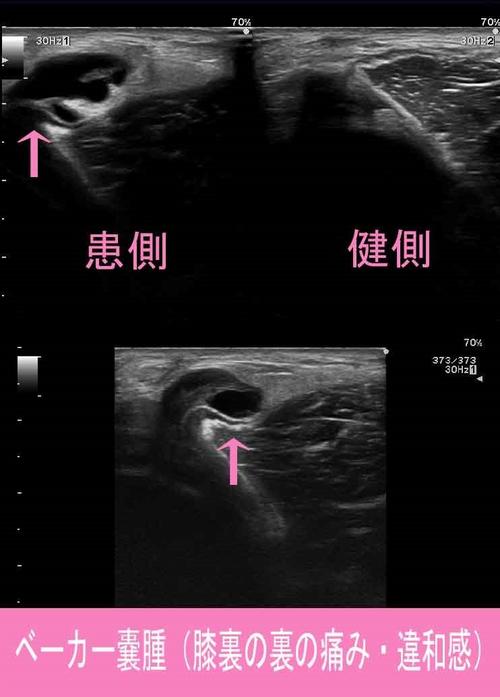

ベーカー嚢腫とは膝の裏側の腓腹筋内側頭と半膜様筋の間に存在する、

滑液包内で炎症が起こり液体が貯留し腫瘤になった状態。

訴えとしては「膝の後ろにできものができた」

「膝を曲げると違和感がある」といったものが多いです。

50代の女性に多く、しばしば関節腔と交通していますが、

ベーカー側から関節腔側への交通はほとんどありません。

ベーカー嚢腫1.jpg